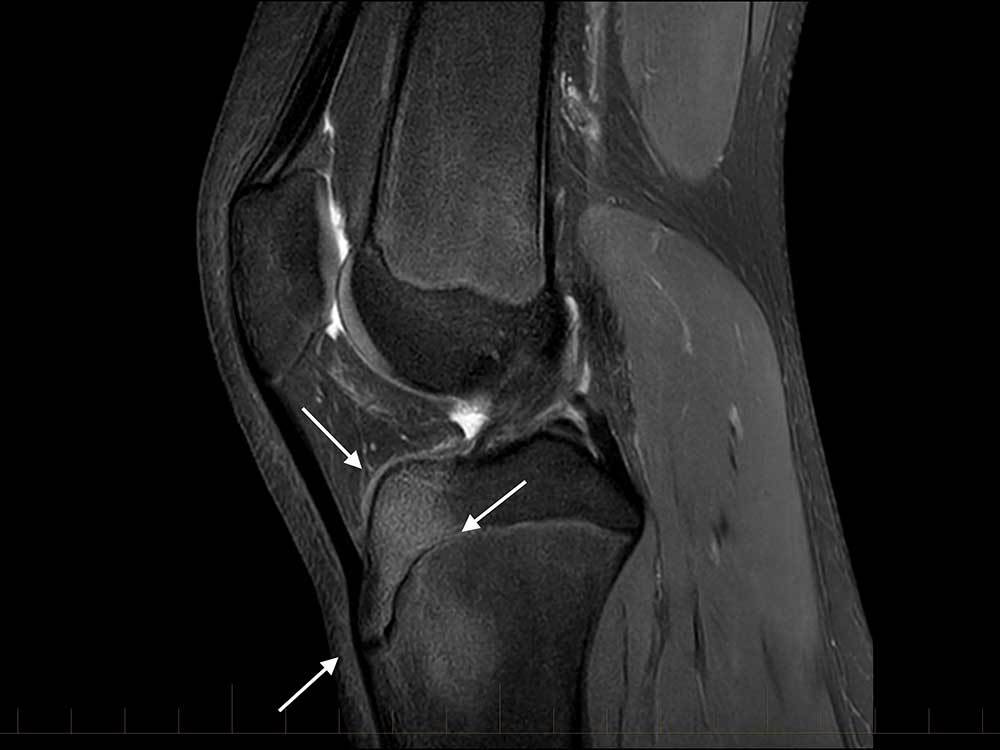

Meniscal root tear

Tear at the junction of the posterior horn medial meniscus and its attachment of the tibial eminence. This is known as the meniscal root.

Case Discussion

These tears are unusual and occur either as an acute injury in young patients or as a degenerative process in older patients. As the meniscus is reasonably well vascularised at the root, surgical repair is recommended in younger patients. In older patients with degeneration there is often associated chondral damage thus repair is more problematic and can fail.

Meniscal root tears are a type of meniscal tear in the knee where the tear extends to either the anterior or posterior meniscal root attachment to the central tibial plateau. They often tend to be radial tears extending into the meniscal root.

Best assessed on T2 weighted sequences. When it involves the posterior root, medial root tears are easier to diagnose than lateral root tears.

On medial posterior root tears there is often 2:

shortening or absence of the root on sagittal images

vertical fluid cleft on coronal fluid-sensitive (T2) images

On posterior root radial tears of the lateral meniscus, the appearance may be similar to radial tears in other locations.

For root tears in general, sagittal imaging may demonstrate a meniscal ghost sign.

Other features include:

truncation sign on coronal images 4

features meniscal extrusion on coronal plane 4